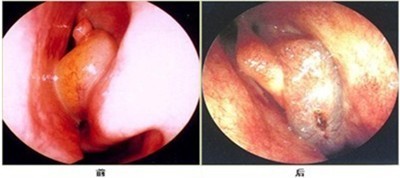

鼻窦炎的临床诊断和结果(以下图片可能引起不适,请谨慎浏览)

鼻内窥镜检查可见鼻粘膜慢性充血肿胀,鼻窦开口的区域可见有脓性分泌物,鼻窦透照,患病鼻窦透光不好。同时,检查可见患病鼻窦腔内密度均匀增高。

(图示:鼻窦炎前、后期的鼻内窥镜成像图)

鼻窦炎如果长期得不到有效的治疗,可引发其他并发症,加大治疗的难度,同时鼻腔长期处于炎症状态,加大了转化鼻咽癌的概率,因此,医生告诉鼻窦炎的患者,较好的预防疾病的方法就是早诊断、早治疗。